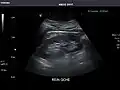

Left kidney -

Kidneys: Right and left kidneys measure 11.5 cm and 12 cm in length respectively. No hydronephrosis. Small left lower pole kidney cyst.